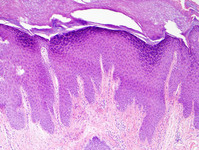

Medium-power photomicrograph of lichen simplex chronicus (haematoxylin-eosin stain, x100)

From the personal collection of Dr Brian L. Swick; used with permission